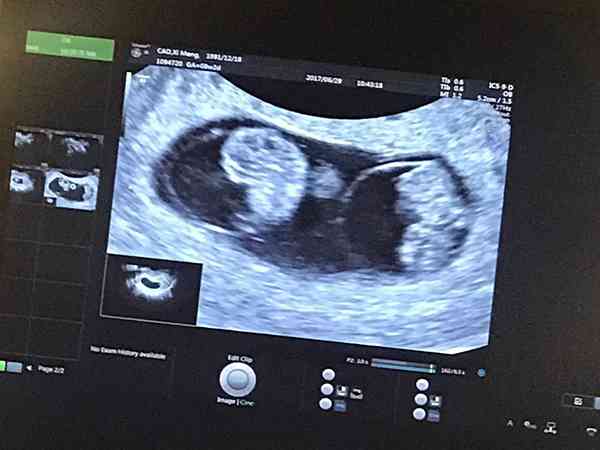

末次月經時間2021年3月26日,預測預產期2021年12月31日,4月29日查的hcg:1985mIU/mL 、孕酮:16.93ng/mL,5月1日查的hcg:3996mIU/mL,孕酮:59.36nmol/L,5月16日hcg:10718mIU/mL 、孕酮:11.19ng/ml,5月23日hcg:10868mIU/mL 、孕酮:20.4ng/mL醫生說我孕酮值不正常,懷雙胞胎孕早期孕酮一般多高才正常?懷雙胞胎孕早期孕酮一般應該在25ng/mg左右,如果低於這個數值說明體內的黃體功能有問題,應該及時尋求醫生幫助,給補充黃體酮進行保胎。不同的懷孕週數孕酮有不同的參照值,孕酮值在懷孕期間就是會隨著時間而升高,一般到了孕八週後就會明顯上升,在足月到達預產期時孕酮可高達160ng/ml,等到胎盤功能開始衰退時,血液中的孕酮值又會慢慢下降。